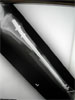

Progress

Distraction of osteotomy site and tibia lengthening